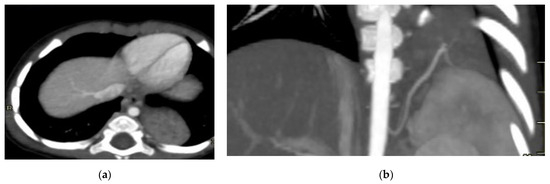

For postnatal evaluation, CT and CT angiography are the methods of choice, as they provide clear visualization of vascularized parenchymal consolidation with arterial supply from the descending or abdominal aorta (Figure 8).

Figure 8.

Intra-lobar bronchopulmonary sequestration. The Contrast-enhanced computed tomography (CECT) axial (a), coronal MPR reconstruction (b), and volume rendering reconstruction (c) images show a parenchymal consolidation located in the lower left lobe supplied by an afferent artery originating from the suprarenal tract of the abdominal aorta. Intraoperative findings confirmed the bronchopulmonary sequestration (d).